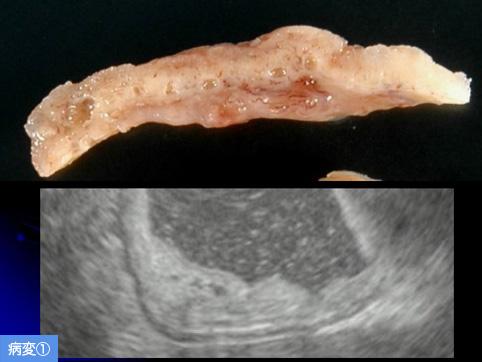

질환(병리주체)의 분류 양성 상피성종양/선종

부위(장기별) 위(부위)/전정

검사방법 초음파

종양의 육안분류 0형(표재형)/IIa형(IIa)

종양의 최대경(밀리미터) 20~24

다발종양(동일 장기) 유(동시성)